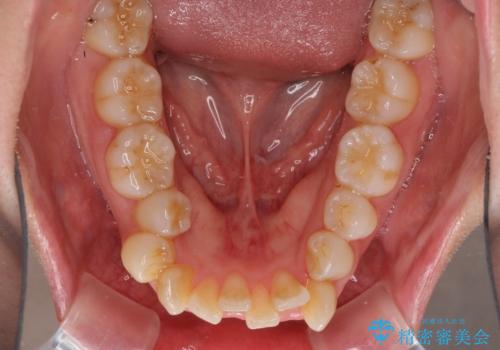

- 前歯のデコボコと口元の突出感を気にして来院された患者様です。

上下左右第一小臼歯4本を抜歯し、ワイヤー装置にて口元を引っ込めるよう矯正治療を行うこととしました。

叢生が強かったため、口元の突出感の改善には限界がありましたが、横側からも口元が引っ込んだ感じが分かるほど改善されました。